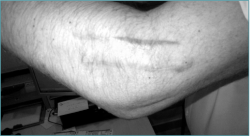

- Cicatrices previas (Figura 2).

Figura 2. Cicatrices por cirugías previas con la posibilidad de existencia de material de osteosíntesis que nos pueden hacer pensar en un caso complejo de rigidez de codo.